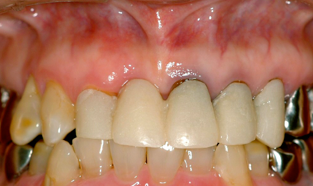

当歯科院症例写真

前歯の差し歯が折れて

抜歯した症例です

どの歯がインプラントかわかりません。

特に前歯のインプラントは審美性が

求められるので、

繊細な技術が必要です。